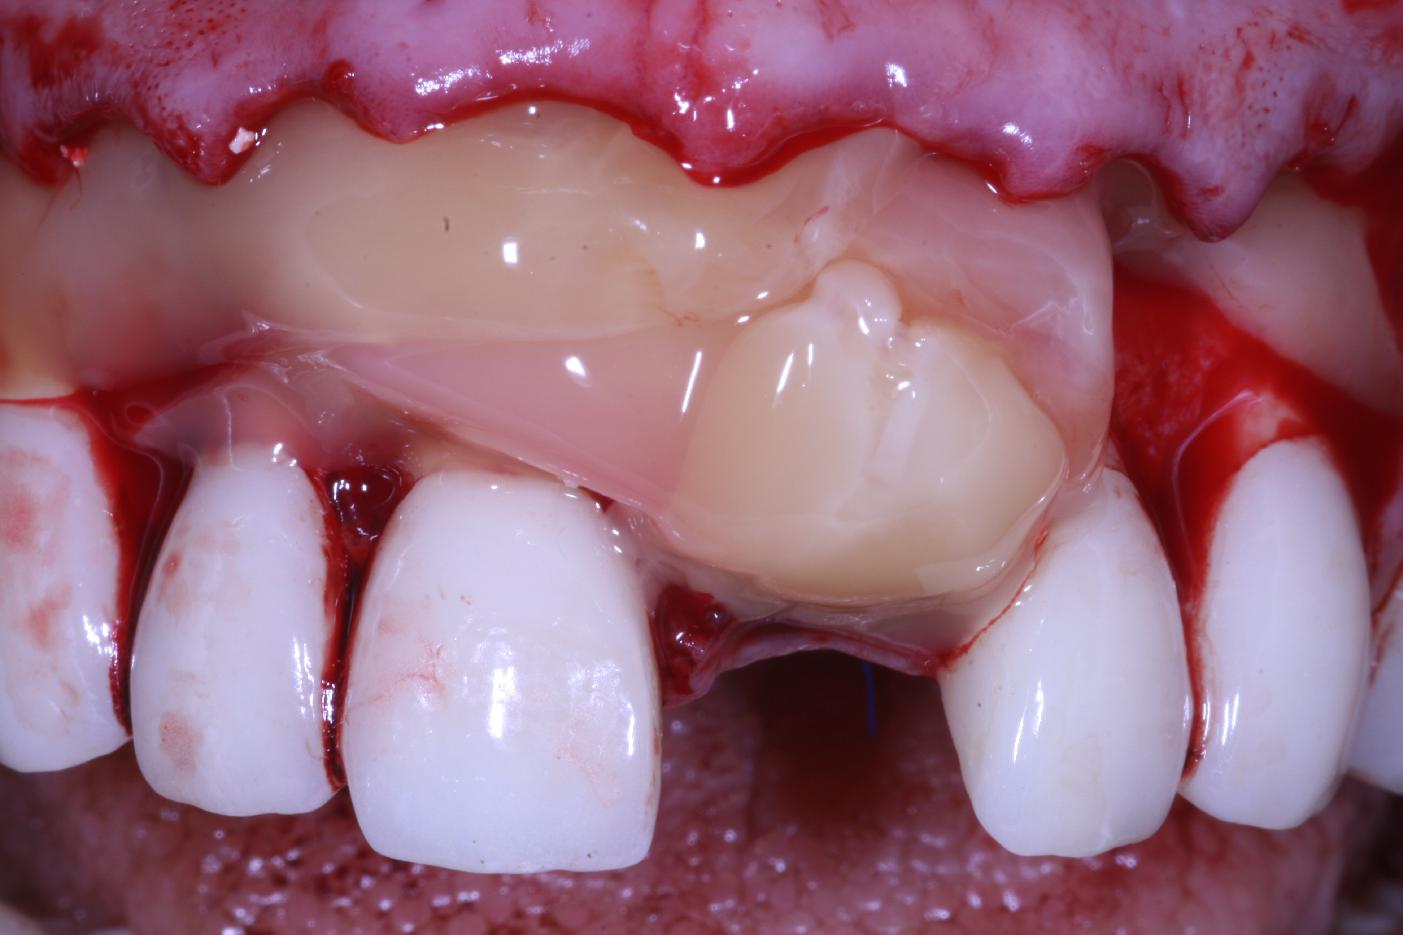

Initial situation: missing teeth #11 & 12 and badly broken #21 root